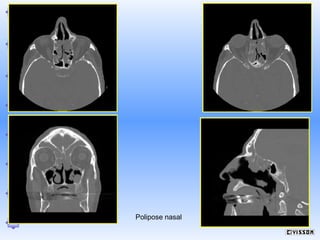

Polipose naso-sinusal

Polipose nasal